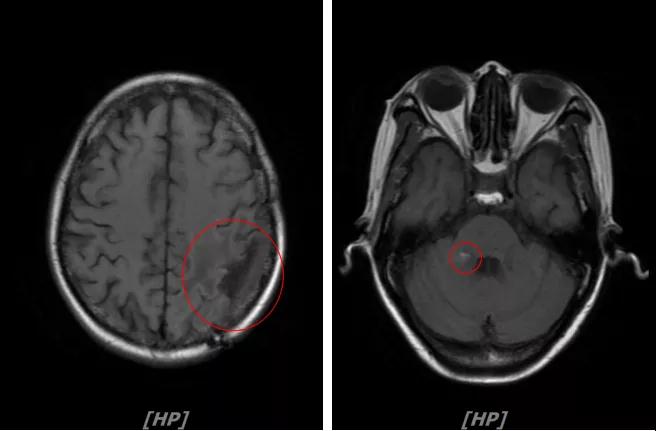

3.病情第2次进展: 2016年12月患者再次出现头痛症状

头颅增强MR:左侧顶枕叶见片状T1WI低信号、T2WI高信号影,增强后病灶边缘见局部斑片状强化改变,邻近脑膜轻度强化改变;右侧脑室三角区内侧见大小约8x14mm的结节影,T1WI低信号、T2WI等高信号,增强明显强化,灶周水肿明显;两侧脑室旁见片状异常信号,T1WI低信号,T2WI高信号,增强未见明显强化,余脑室、脑池、脑沟大小形态可,中线结构居中无移位

左顶叶脑转移瘤术后放疗后,左顶叶术区边缘强化灶;考虑肿瘤复发

右侧脑室三角区内侧转移瘤

两侧脑室旁云絮状异常信号,考虑放疗后改变